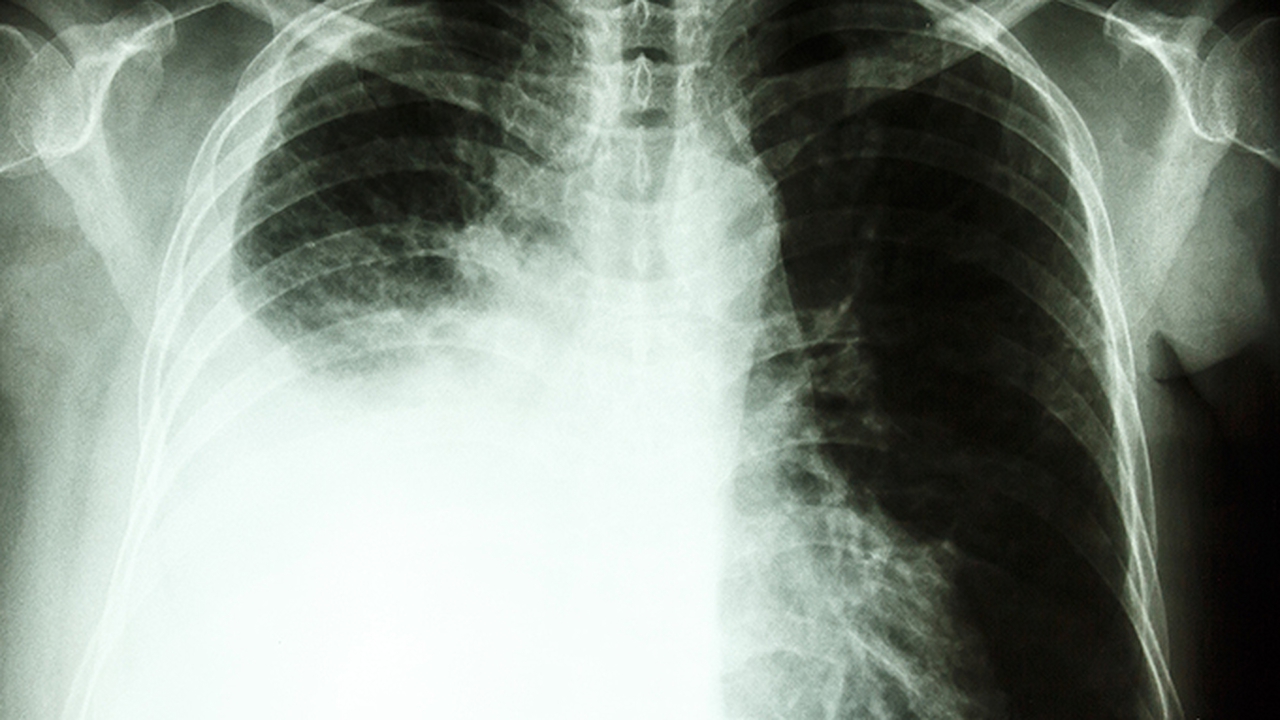

肺结节是一种常见的肺部病变,中医认为其发病与正气不足、痰瘀互结、气滞血瘀等因素有关。中医治疗肺结节注重整体调理,通过辨证施治,采用中药内服、针灸、拔罐等方法,改善患者体质,缓解症状。